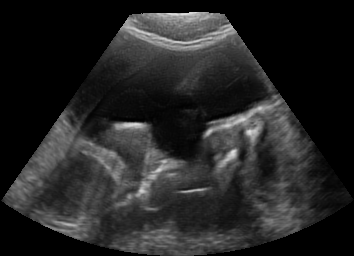

Real in-vivo images. 22 ultrasound sequences were collected using a GE Voluson E8 machine during standard fetal screening exams of 8 patients. Each sequence is several seconds long. We extracted all 4427 frames and resize them to , see Fig. 2 for some examples. The resulting image set was randomly split into training-validation-test sets by a 80-10-10% ratio.